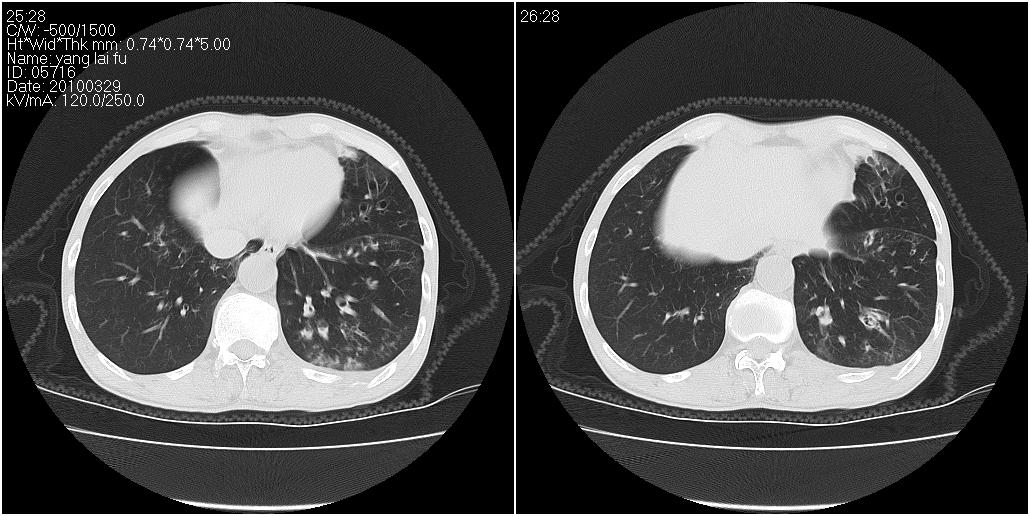

1)右肺中叶慢性炎症并支气管扩张,节段性肺不张。2)两肺下叶支气管扩张。